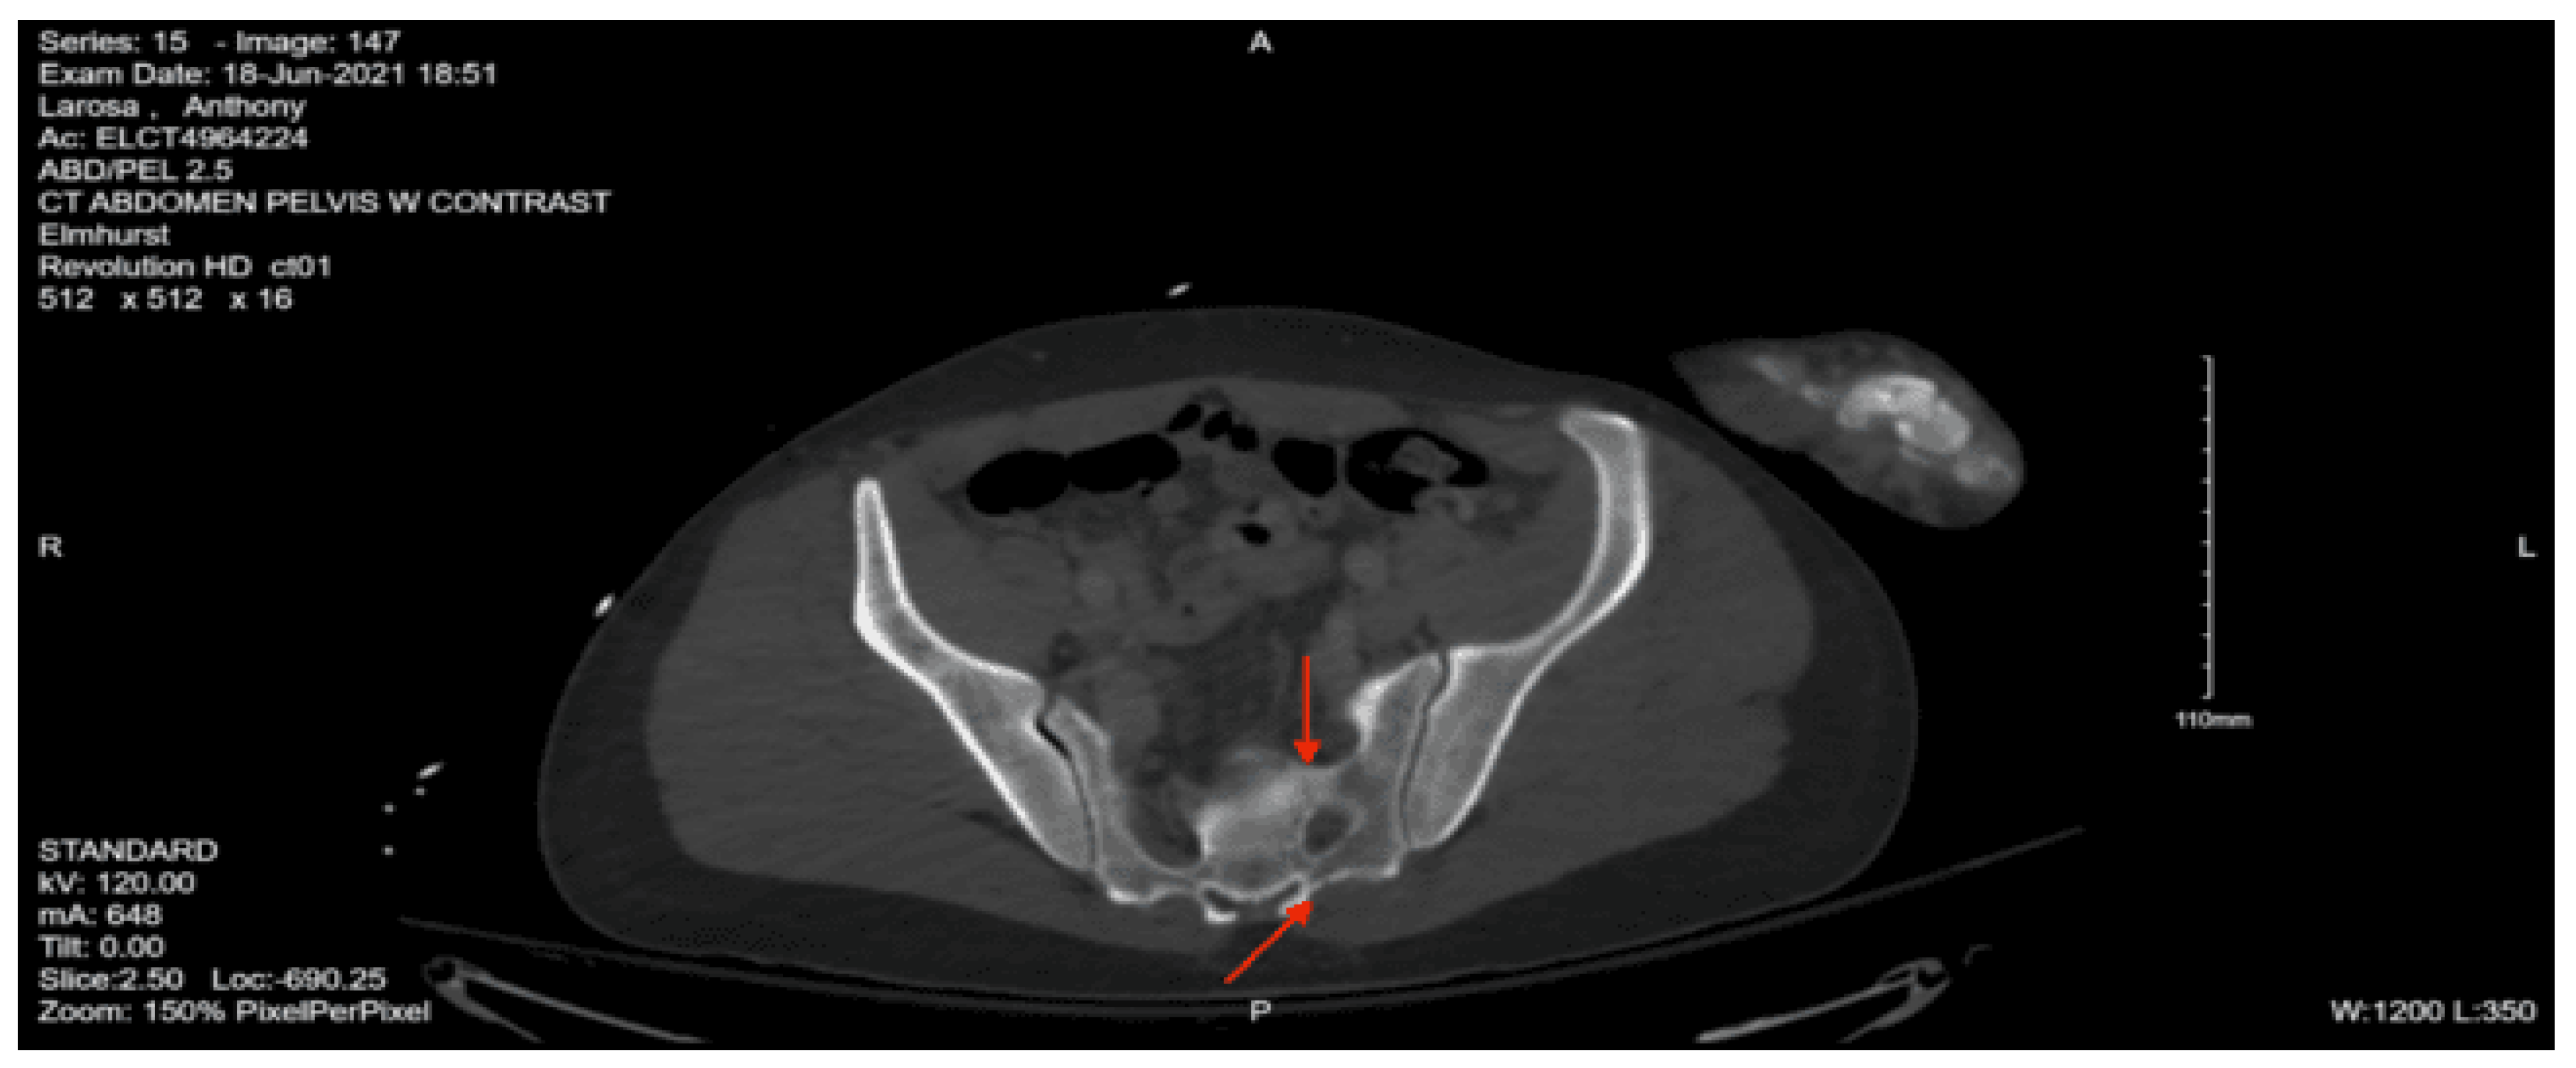

Imaging as shown in Figure 1, Figure 2 and Figure 3:

CT abdomen/pelvis with contrast: Acute fractures are seen involving the right superior pubic ramus and left inferior pubic ramus. An acute comminuted avulsed fracture of the left sacral wing in the superior and midportion is demonstrated. No definitive acute traumatic visceral abnormalities were found throughout the abdomen and pelvis.

DX: Denis zone II left sacral alar fx involving S1 foramina. AOSpine B3: NX, M3